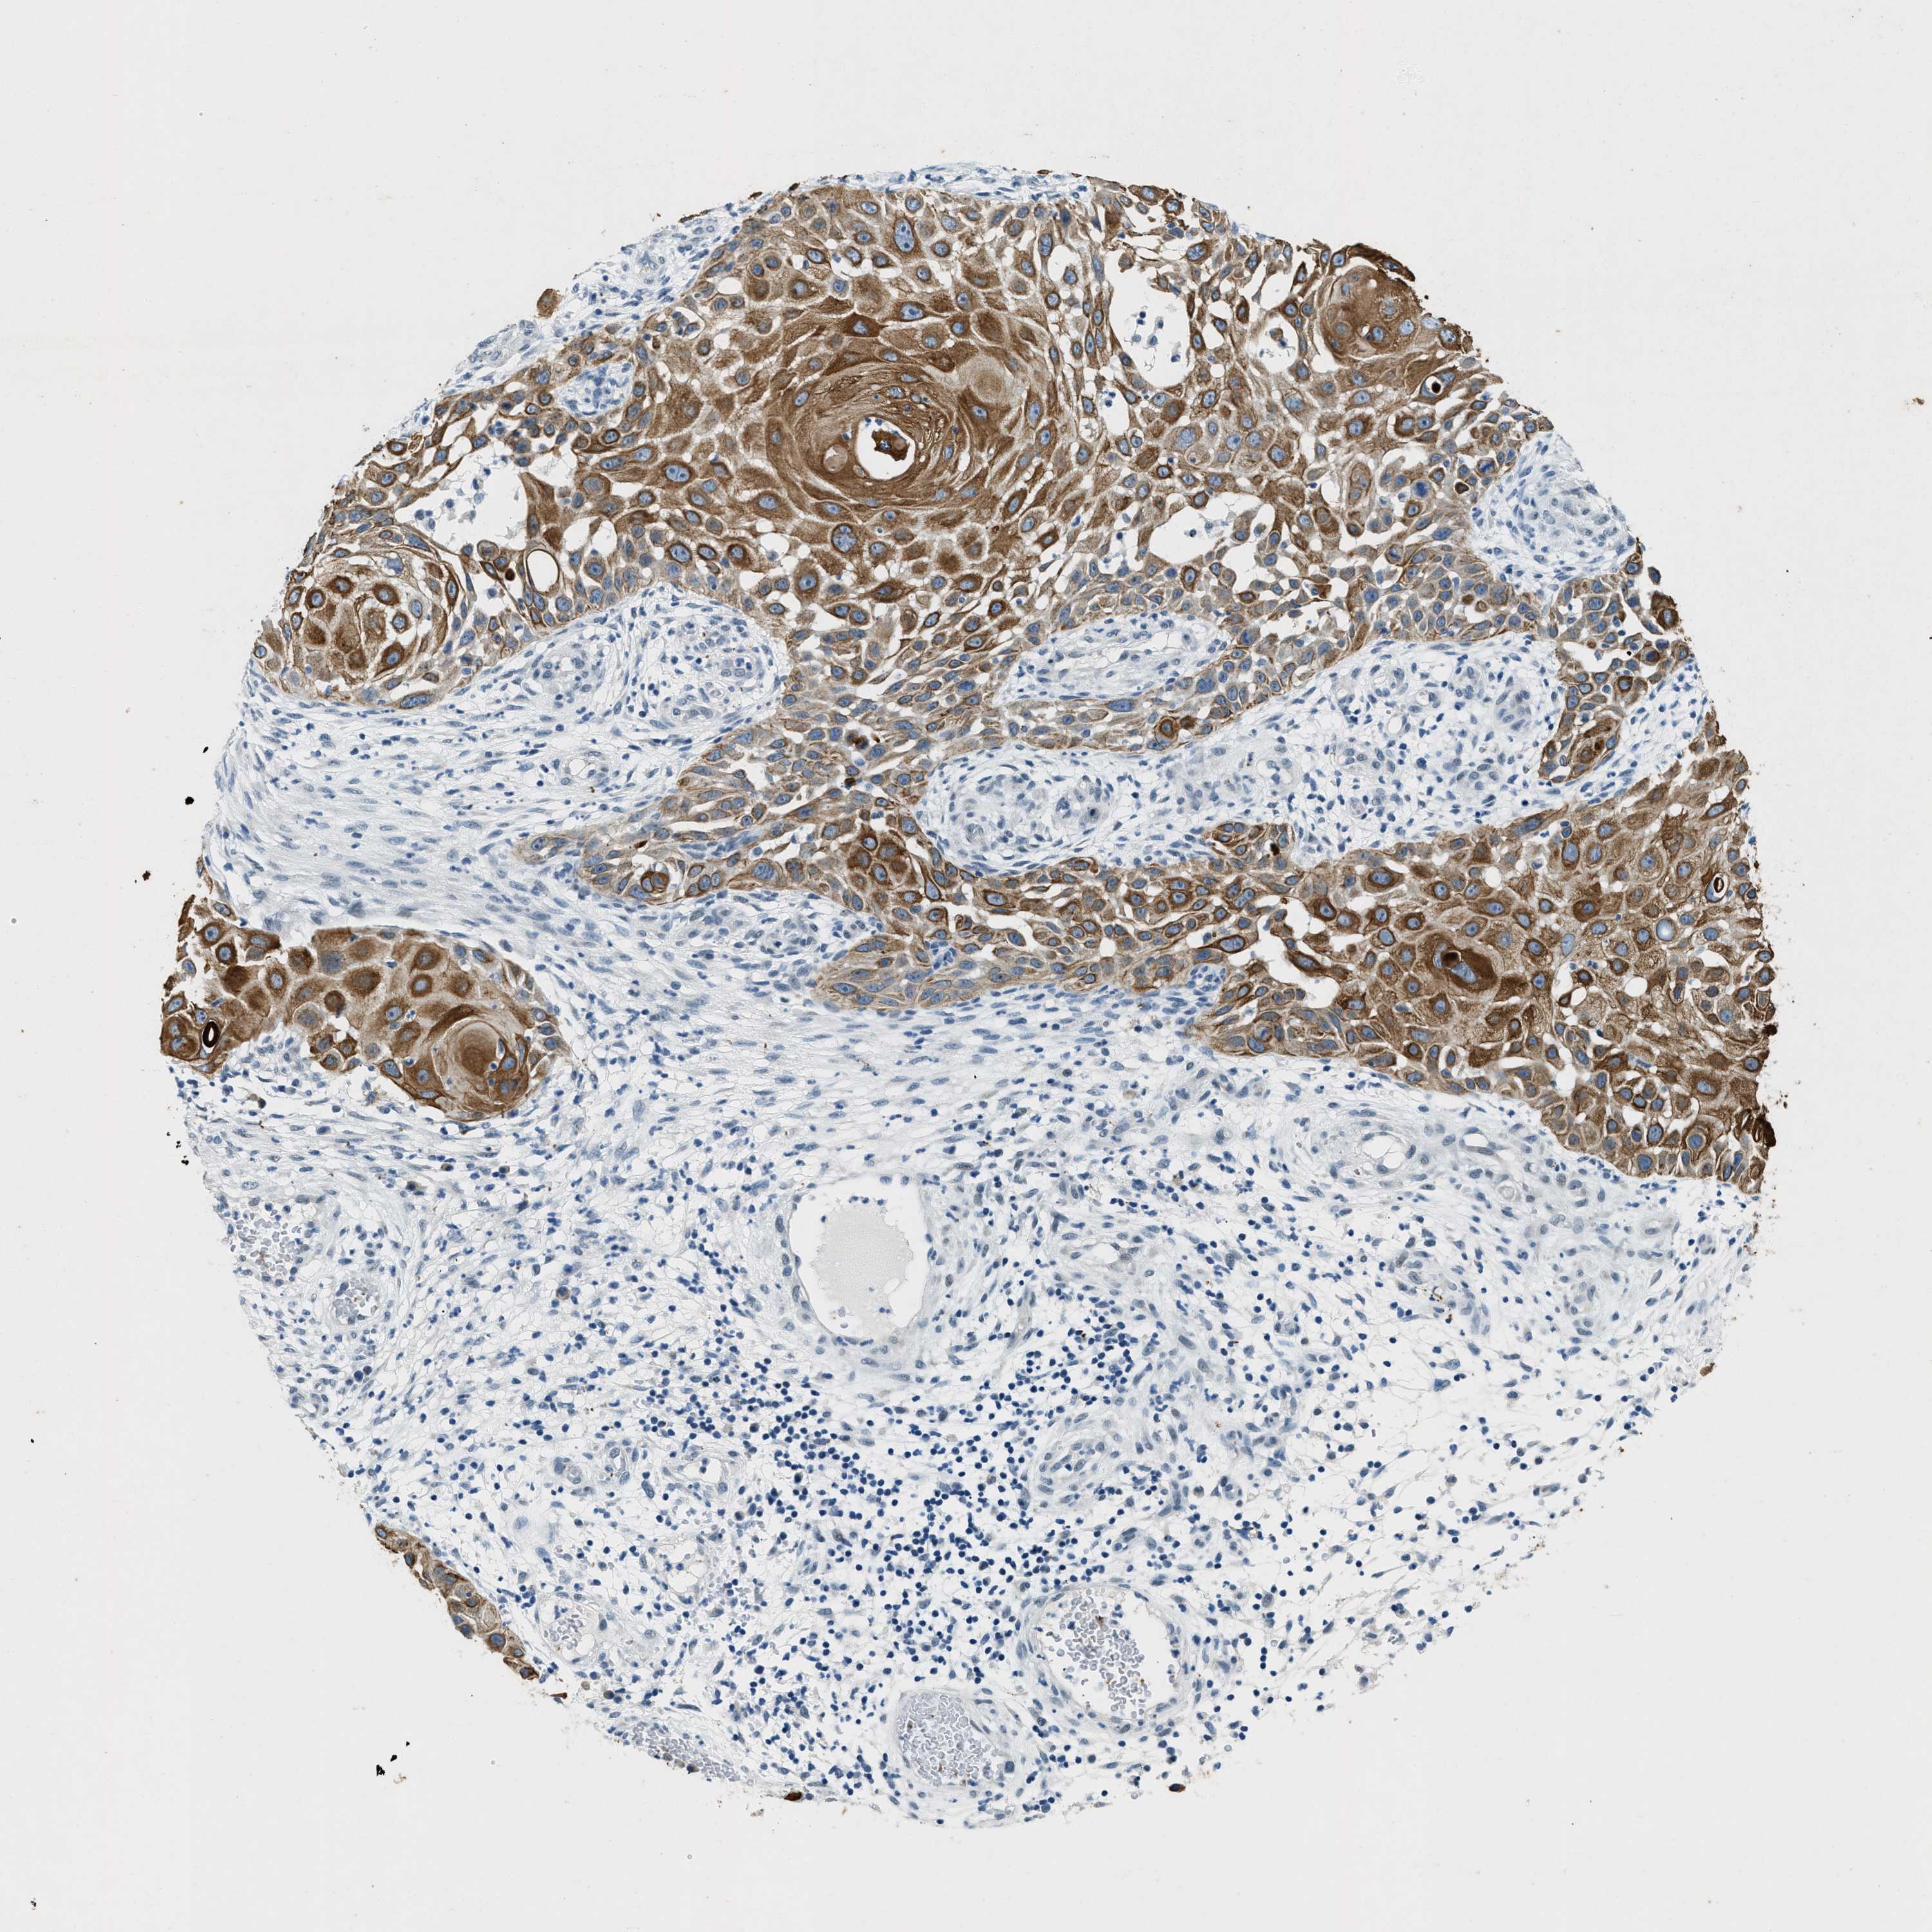

SKIN CANCER - Protein expressioni

A mouse-over function shows sample information and annotation data. Click on an image to view it in a full screen mode. Samples can be filtered based on level of antibody staining by selecting one or several of the following categories: high, medium, low and not detected. The assay and annotation is described here.

Antibody stainingi

Antibody staining in the annotated cell types in the current human tissue is reported as not detected, low, medium, or high, based on conventional immunohistochemistry profiling in selected tissues. This score is based on the combination of the staining intensity and fraction of stained cells.

Each image is clickable and will lead to virtual microscopy that enables deeper exploration of all samples and also displays staining intensity scores, fraction scores and subcellular localization as well as patient and tissue information for each sample.

Antibody HPA018195

Staining

High

Medium

Low

Not detected

Intensity

Strong

Moderate

Weak

Negative

Quantity

>75%

75%-25%

<25%

None

Location

Nuclear

Cytoplasmic/membranous

Cytoplasmic/membranous,nuclear

Squamous cell carcinoma, metastatic, NOS